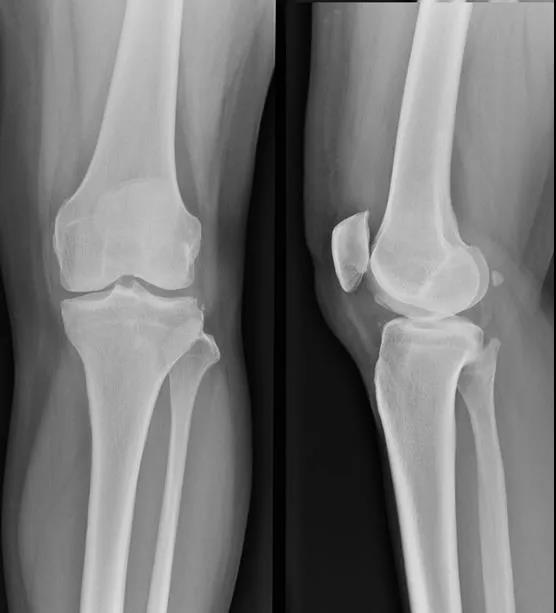

膝关节穿刺术常用于检查关节腔内积液的性质,或抽液后向关节腔内注药。膝关节腔内积液,需行关节穿刺抽液检查或引流,或注射药物进行治疗。关节腔内注射空气或造影剂,行关节造影术,以了解关节软骨或骨端的变化。

1、以髌骨中心点,作水平线和垂直线,其第一和第二象限,各做45度的平分角,该平分线与髌骨内外缘的交点,即是进针点。

2、患者仰卧位,膝关节伸直,髌骨上缘与髌骨内外侧缘的交点为两点,斜向髌股关节中心,以45°角穿刺。

髌骨外上缘穿刺法

定位:髌骨外上缘处与股外侧肌交界处。按压股外侧肌下凹陷处,贴指甲刺入0.5-1cm,有落空感即可。

髌骨外下缘(外侧膝眼)穿刺法

定位:屈膝90°位,髌骨下缘、髌韧带外侧1cm处(外侧膝眼,可看到一小凹陷)。